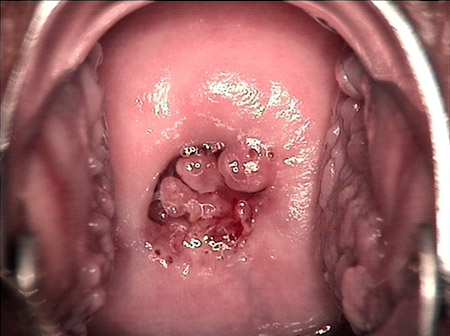

• 宮頸息肉宮頸息肉

• 宮頸息肉 leep術(shù)后宮頸息肉 leep術(shù)后